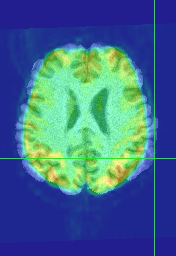

Regarding sub96591. When I run flirt with 6 dof I get poor registration (see attached). The mprage is wider by about 5-8 mm on either side. I guess it could be severe distortion but the epi looks pretty good.

Regarding flipping. This is hard to see, but examine sub64202. There are some very deep sulci in the right inferior frontal area, which makes it easier to see the alignment.

Then load the registered mprage in to AFNI and overlay the flipped epi. Look at slice 72-75 on the aligned mprage and look for the very deep sulcus in the right frontal cortex. You should see the contour matches on the epi overlay. It helps to rapidly toggle the visibility of the epi overlay.

Note that flirt does not do well with these images as it tends to push the epi up in the z plane 5 to 10mm. This makes it hard to see the left-right flip.